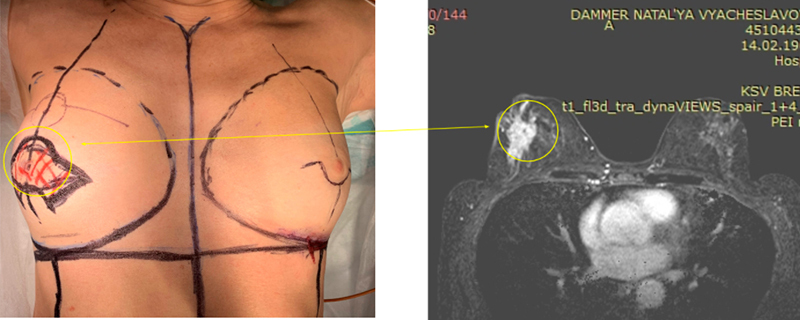

В декабре 2020 года ко мне обратилась 55 летняя женщина с жалобами на наличие опухоли в правой молочной железе. В 1й день я сделал ей биопсию опухоли и МРТ молочных желез с контрастом. Параллельно она сдала анализ крови на определение мутации гена BRCA 1,2. В случае наличия мутации женщинам обычно рекомендуют выполнить удаление здоровой молочной железы и яичников (помните Анжелину Джоли). Для исключения метастазов на 2й день мы выполнили ей КТ легких и органов брюшной полости и МРТ головного мозга. Результаты показали что все *чисто*. Гистология уже была готова на 3-й день. К сожалению анализ показал, что это рак. Но были и хорошие новости. ИГХ (иммуногистиохимическое исследование) показало, что у женщины самый благоприятный тип опухоли: люминальный А. Такой рак молочной железы во многих странах не является смертельным. Опухоль обладает высокой чувствительностью к гормонам, низкой скоростью деления опухолевых клеток.

В таких случаях на первом этапе лечение начинают с операции. Мы остановились на подкожной двусторонней мастэктомии (когда удаляют железу без удаления кожи) с одномоментным эндопротезированием имплантами. В ее случае мы поставили полиуретановые импланты по 265 мл. Для того что бы понять нужна ли ей будет лучевая терапия мы выполнили удаление поверхностной группы подмышечных лимфоузлов (отек руки в таких случаях не развивается). Операция 2 часа, кровопотери нет. Первая перевязка будет на 3й ил 4й день. Пациентка готовиться к выписке.

В таких случаях на первом этапе лечение начинают с операции. Мы остановились на подкожной двусторонней мастэктомии (когда удаляют железу без удаления кожи) с одномоментным эндопротезированием имплантами. В ее случае мы поставили полиуретановые импланты по 265 мл. Для того что бы понять нужна ли ей будет лучевая терапия мы выполнили удаление поверхностной группы подмышечных лимфоузлов (отек руки в таких случаях не развивается). Операция 2 часа, кровопотери нет. Первая перевязка будет на 3й ил 4й день. Пациентка готовиться к выписке.